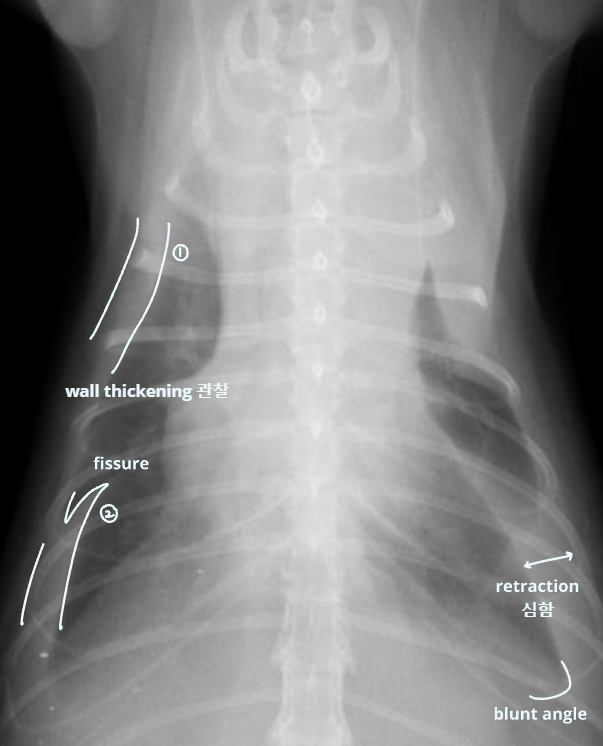

4. Pleural Space

| Pleural effusion (ํ์) | Pneumothorax (๊ธฐํ) | |

| ํ๊ฐ(pleural cavity)์ ๋ฌผ์ด ์ฐฌ ๊ฒ (ํ์ ์ฐจ๋ฉด โ ํ์์ข ) | ํ๊ฐ์ ๊ณต๊ธฐ๊ฐ ์ฐฌ ๊ฒ (ํ์ ์ฐจ๋ฉด โ ํ๊ธฐ์ข ) | |

| Radiographic signs interlobar fissure ๋๊ป๊ฒ ๊ด์ฐฐ๋๊ณ , ํ๋ฒฝ์ด ๋จ์ด์ ธ ๋๊ฐ ๊ฒ์ฒ๋ผ ๋ณด์ | Radiographic signs ์ฌ์ฅ์ด ๋ ์๊ณ , ํ๊ฐ ์ชผ๊ทธ๋ผ๋ฆ | |

| - Interlobar fissure widening - Lung retraction - Pleural wall thickening - Scallop sign - Cardiac effacement - Blunt angle | - Retraction of pleural surface - Collapsed lung (โ opacity ์ฆ๊ฐ) | |

![]() | ![]() | |

![]() |